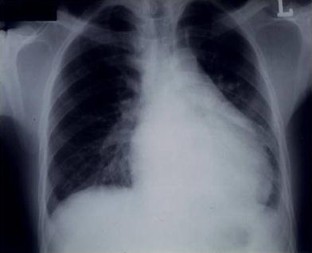

Fig. 1